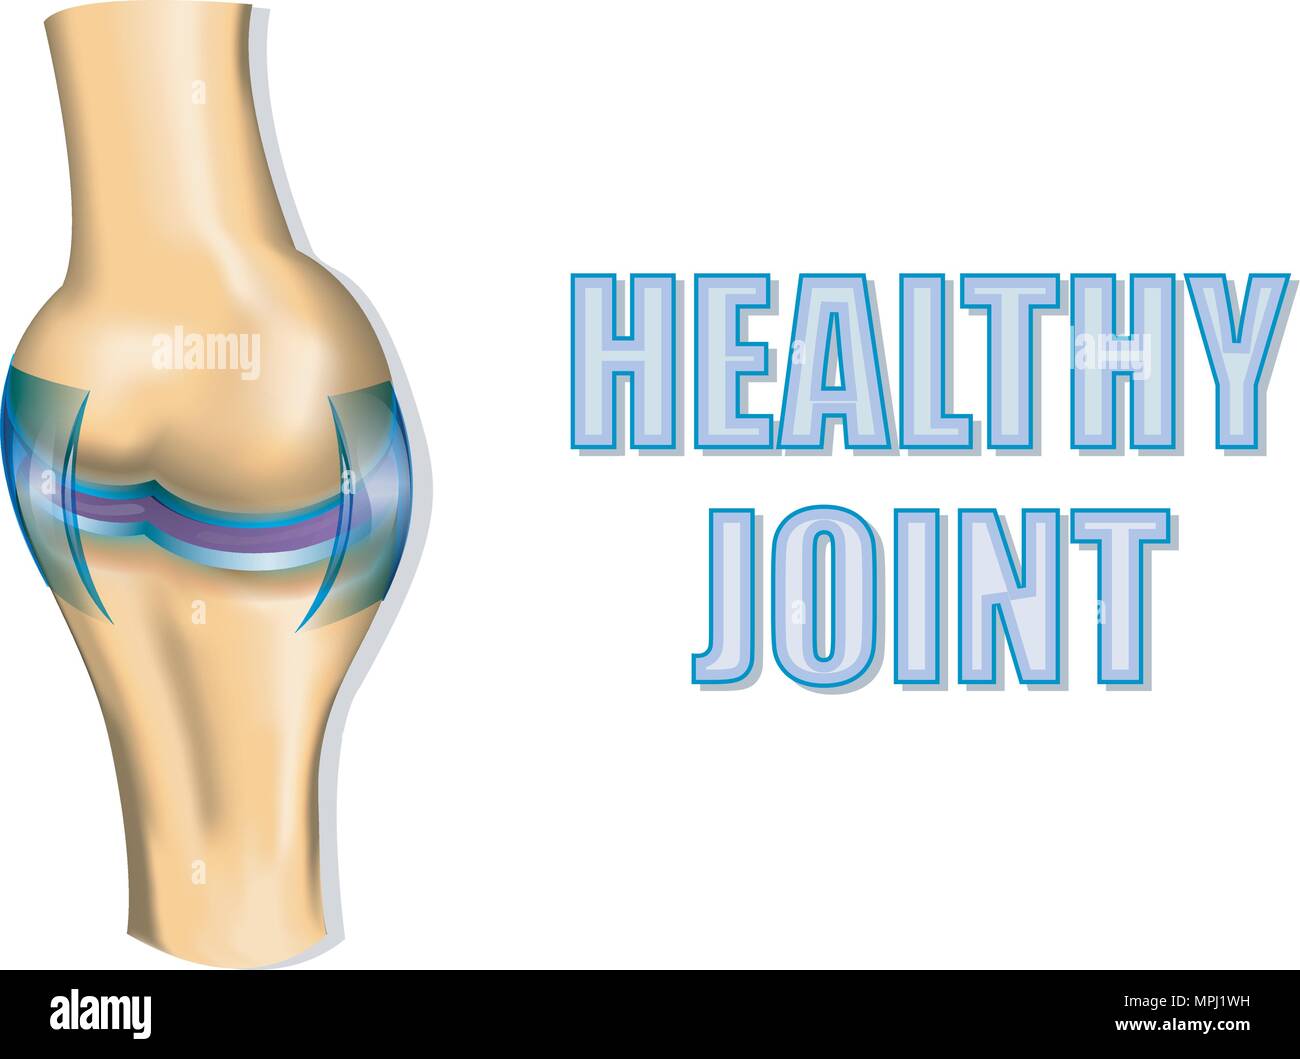

ILLUSTRATION OF THE HEALTHY JOINT. CUTAWAY VIEW. Stock Vectorhttps://www.alamy.com/image-license-details/?v=1https://www.alamy.com/illustration-of-the-healthy-joint-cutaway-view-image186022749.html

ILLUSTRATION OF THE HEALTHY JOINT. CUTAWAY VIEW. Stock Vectorhttps://www.alamy.com/image-license-details/?v=1https://www.alamy.com/illustration-of-the-healthy-joint-cutaway-view-image186022749.htmlRFMPJ1WH–ILLUSTRATION OF THE HEALTHY JOINT. CUTAWAY VIEW.